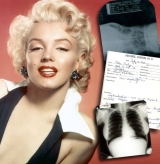

Marilyn Monroe: belleza... ¿natural?

El médico Michael Gurdin sacó a la luz pública reveladores informes médicos, que serán subastados en Beverly Hills, que demuestran que la actriz se sometió a un implante de cartílago en su barbilla en 1950 con el fin de potenciar su atractivo físico.